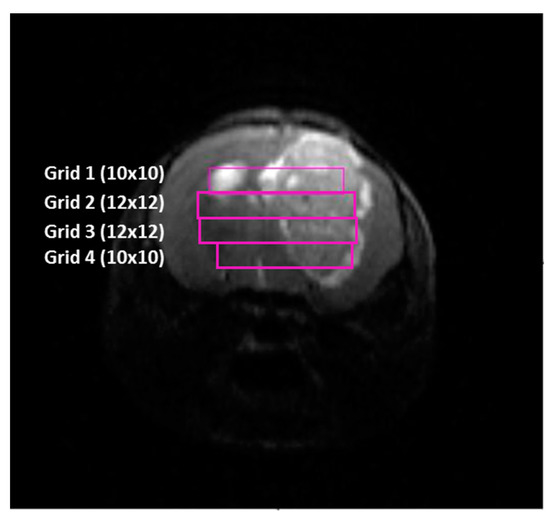

4.4.2. MRI and MRSI Processing and Post Processing